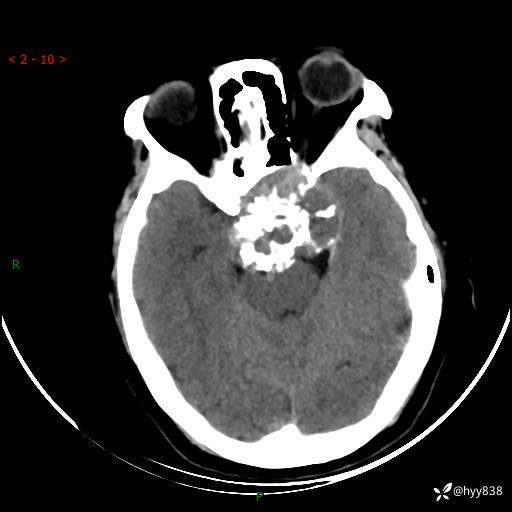

老年女性,视力下降3年。鞍区钙化性肿块,鉴别诊断有哪些---(有结果)

简要病史:患者3年前无明显诱因左眼出现视力下降,出现视物模糊,无头痛,无头晕,无恶心、呕吐,无意识障碍,无肢体麻木及抽搐,无心慌、胸闷,无腹痛、腹胀等不适,无旋地转感。个月前右眼视力下降,患者视物模糊逐渐下降,自诉看东西有雾感。在当地医院眼科就诊,症状无好转,行头部MR提示:鞍区肿物。现患者为求诊治来我科就诊,在当地市中医医院行头部CT:提示鞍区占位。患者现求进一步诊治来我院就诊,门诊以“鞍区肿物”收入我科。 患病以来,患者精神、饮食、睡眠尚欠佳,大小便如常,体力体重无明显变化。

临床诊断:鞍区肿物

颅脑CT平扫